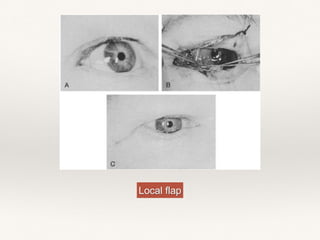

b. Primary closure or SSG or local flaps are used to cover the defect.

Local flap